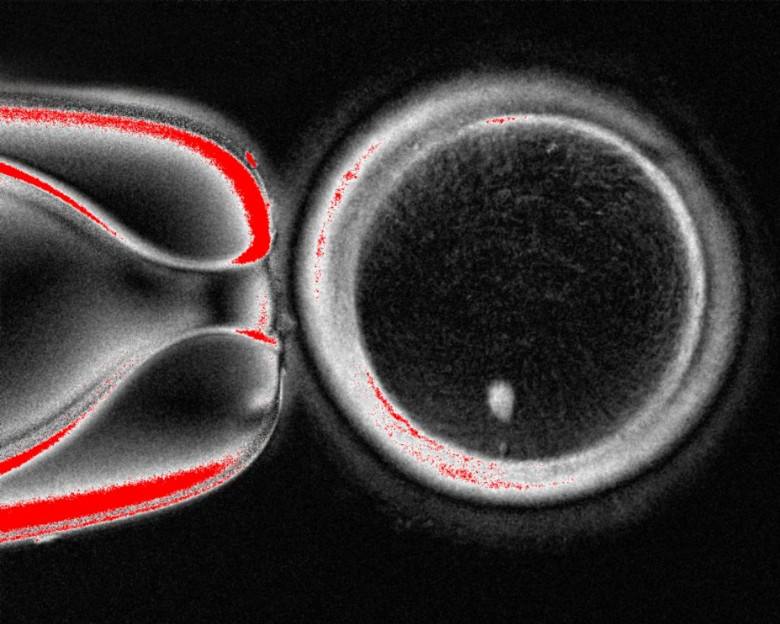

Яйцеклетки из кожи ученые сделали невозможное Исследователи из Орегонского университета здравоохранения превратили клетки человеческой кожи в полноценные яйцеклетки и даже получили из них эмбрионы Правда с оговорками все эмбрионы оказались нежизнеспособными из за хромосомных аномалий Но сам факт мы научились делать яйцеклетки буквально из кожи Технология использует тот же принцип что применялся для создания овечки Долли в 1997 году Берется обычная клетка кожи взрослого человека из неё извлекается ядро с полным набором ДНК Это ядро пересаживают в донорскую яйцеклетку из которой предварительно удалили собственное ядро Получается гибридная клетка оболочка яйцеклетки с ядром от кожи Тут начинается самое сложное В обычной клетке кожи 46 хромосом а в яйцеклетке должно быть 23 Иначе после оплодотворения сперматозоидом еще 23 хромосомы получится эмбрион с избыточным набором 69 вместо 46 Такой организм нежизнеспособен Ученые разработали метод митомейоз комбинацию электрического импульса и препарата росковитин которые заставляют клетку избавиться от половины хромосом Проблема в том что клетка сбрасывает хромосомы как попало Нужны правильные 23 а не случайный набор Из 82 полученных яйцеклеток все после оплодотворения дали эмбрионы с хромосомными ошибками Впрочем 9 эмбрионов дожили до стадии бластоцисты это 6 й день развития когда при ЭКО эмбрион пересаживают в матку На этом этапе эксперимент остановили Зачем это нужно Потенциально революция в лечении бесплодия Женщины после химиотерапии с генетическими аномалиями или просто в возрасте смогут получить собственные яйцеклетки из клеток кожи Однополые пары смогут иметь генетически родных детей создавая яйцеклетки из мужских клеток или сперматозоиды из женских Этические вопросы огромны Биоэтики предупреждают о риске фермерства эмбрионов массового производства зародышей для выбора лучшего Теоретически любой человек в любом возрасте сможет завести ребенка В сочетании с генетическим редактированием это открывает дверь к дизайнерским младенцам Так что пока это больше наука ради науки Но от этого и удивительнее как мир трансформируется в ближайшие 20 лет vselennayaplus